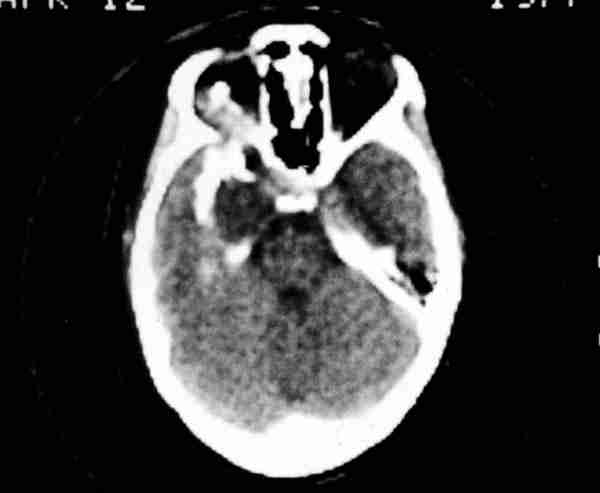

Figura 8. Las técnicas neurorradiológicas son fundamentales en la

cirugía de la órbita.